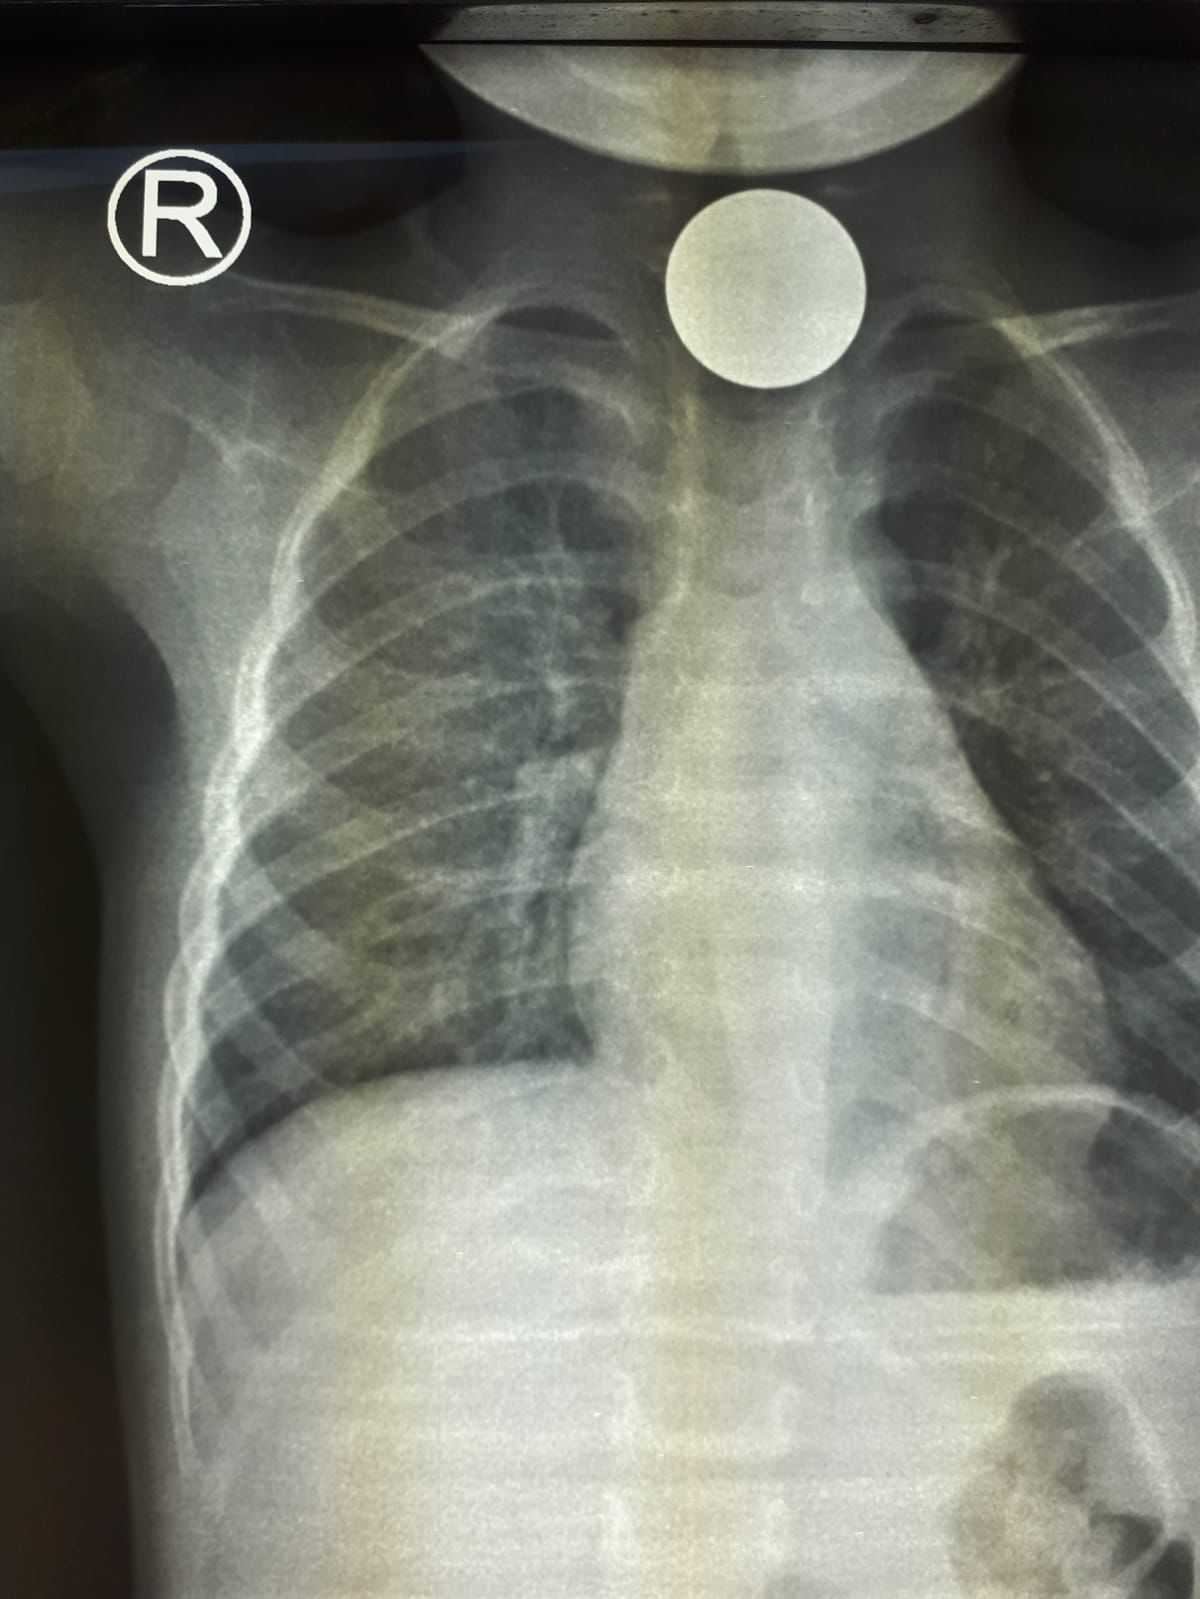

تدخل طبي عاجل بمستشفى رابغ العام لإنقاذ طفل ابتلع عملة معدنية

تمكن - بفضل الله - فريق طبي بمستشفى رابغ العام من استخراج قطعة معدنية من بلعوم طفل يبلغ من العمر عامان خلال عملية لم تستغرق أكثر من 10 دقائق.

وأوضحت (صحة جدة) أن الطفل قَدِم إلى طوارئ المستشفى وهو يشكو ابتلاع جسم غريب (قطعة نقود معدنية) كانت قد علقت في منطقة البلعوم؛ مما تسبب في اختناق وعدم قدرة على البلع؛ حيث قرر الطاقم الطبي إجراء عملية عاجلة بالمنظار لإزالة الجسم الغريب، والتي تبين أنها قطعة معدنية نقدية، وقد كُللت العملية بالنجاح  دون حدوث مضاعفات - ولله الحمد - وقد غادر الطفل المستشفى وهو بصحة جيدة.